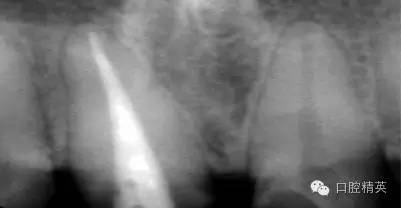

根管治療更是牙體修復(fù)的基礎(chǔ),根據(jù)術(shù)前診斷,對需要做根管治療的或有必要重新做根管治療的,一定要做到恰充,消除隱患,避免將來冠修復(fù)好后,出現(xiàn)根尖炎癥的問題(見圖3、4、5)。在基礎(chǔ)工作做好后,接下來開始牙體預(yù)備,根據(jù)跟個人習慣,選擇合適的車針(圖6、7)。